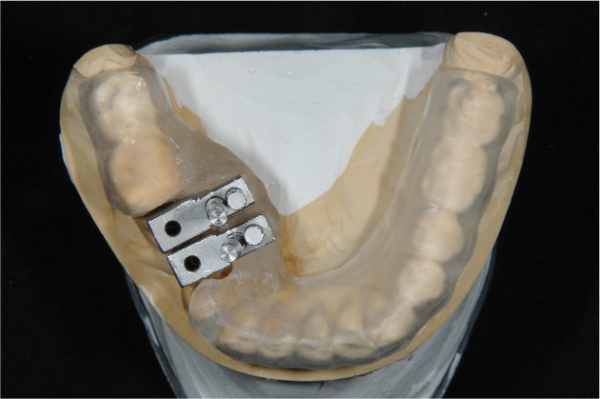

植牙用手術定位器

植牙用手術導板

上面弓與咬合器

咬合器上製作假牙